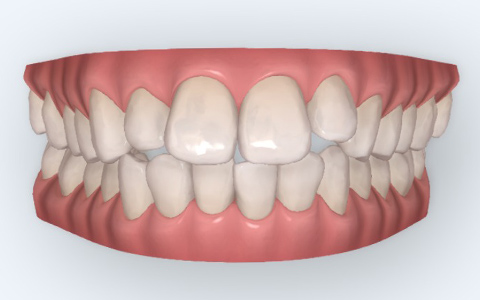

口腔内スキャナー(iTero)を使用して口腔内をスキャンした後に、治療シミュレーションを確認することができます。ただし、あくまで口腔内の変化による影響が考慮されていないシミュレーションとなっておりますので、必ずしもシミュレーション通りの結果になるわけではありません。専門の歯科医師が歯の動かし方や順序をシミュレーションに組み込むことで精度の高い矯正治療が可能となります。

当院では、矯正治療を開始する前に、治療中の経過や治療前後の変化がわかるシミュレーションを実施しております。

口腔内スキャナー(iTero)で採取した3Dデータを用いて、歯がどのように移動しどのように整っていくかを確認することができ、不安なく矯正治療を受けることができます。

治療前

治療後